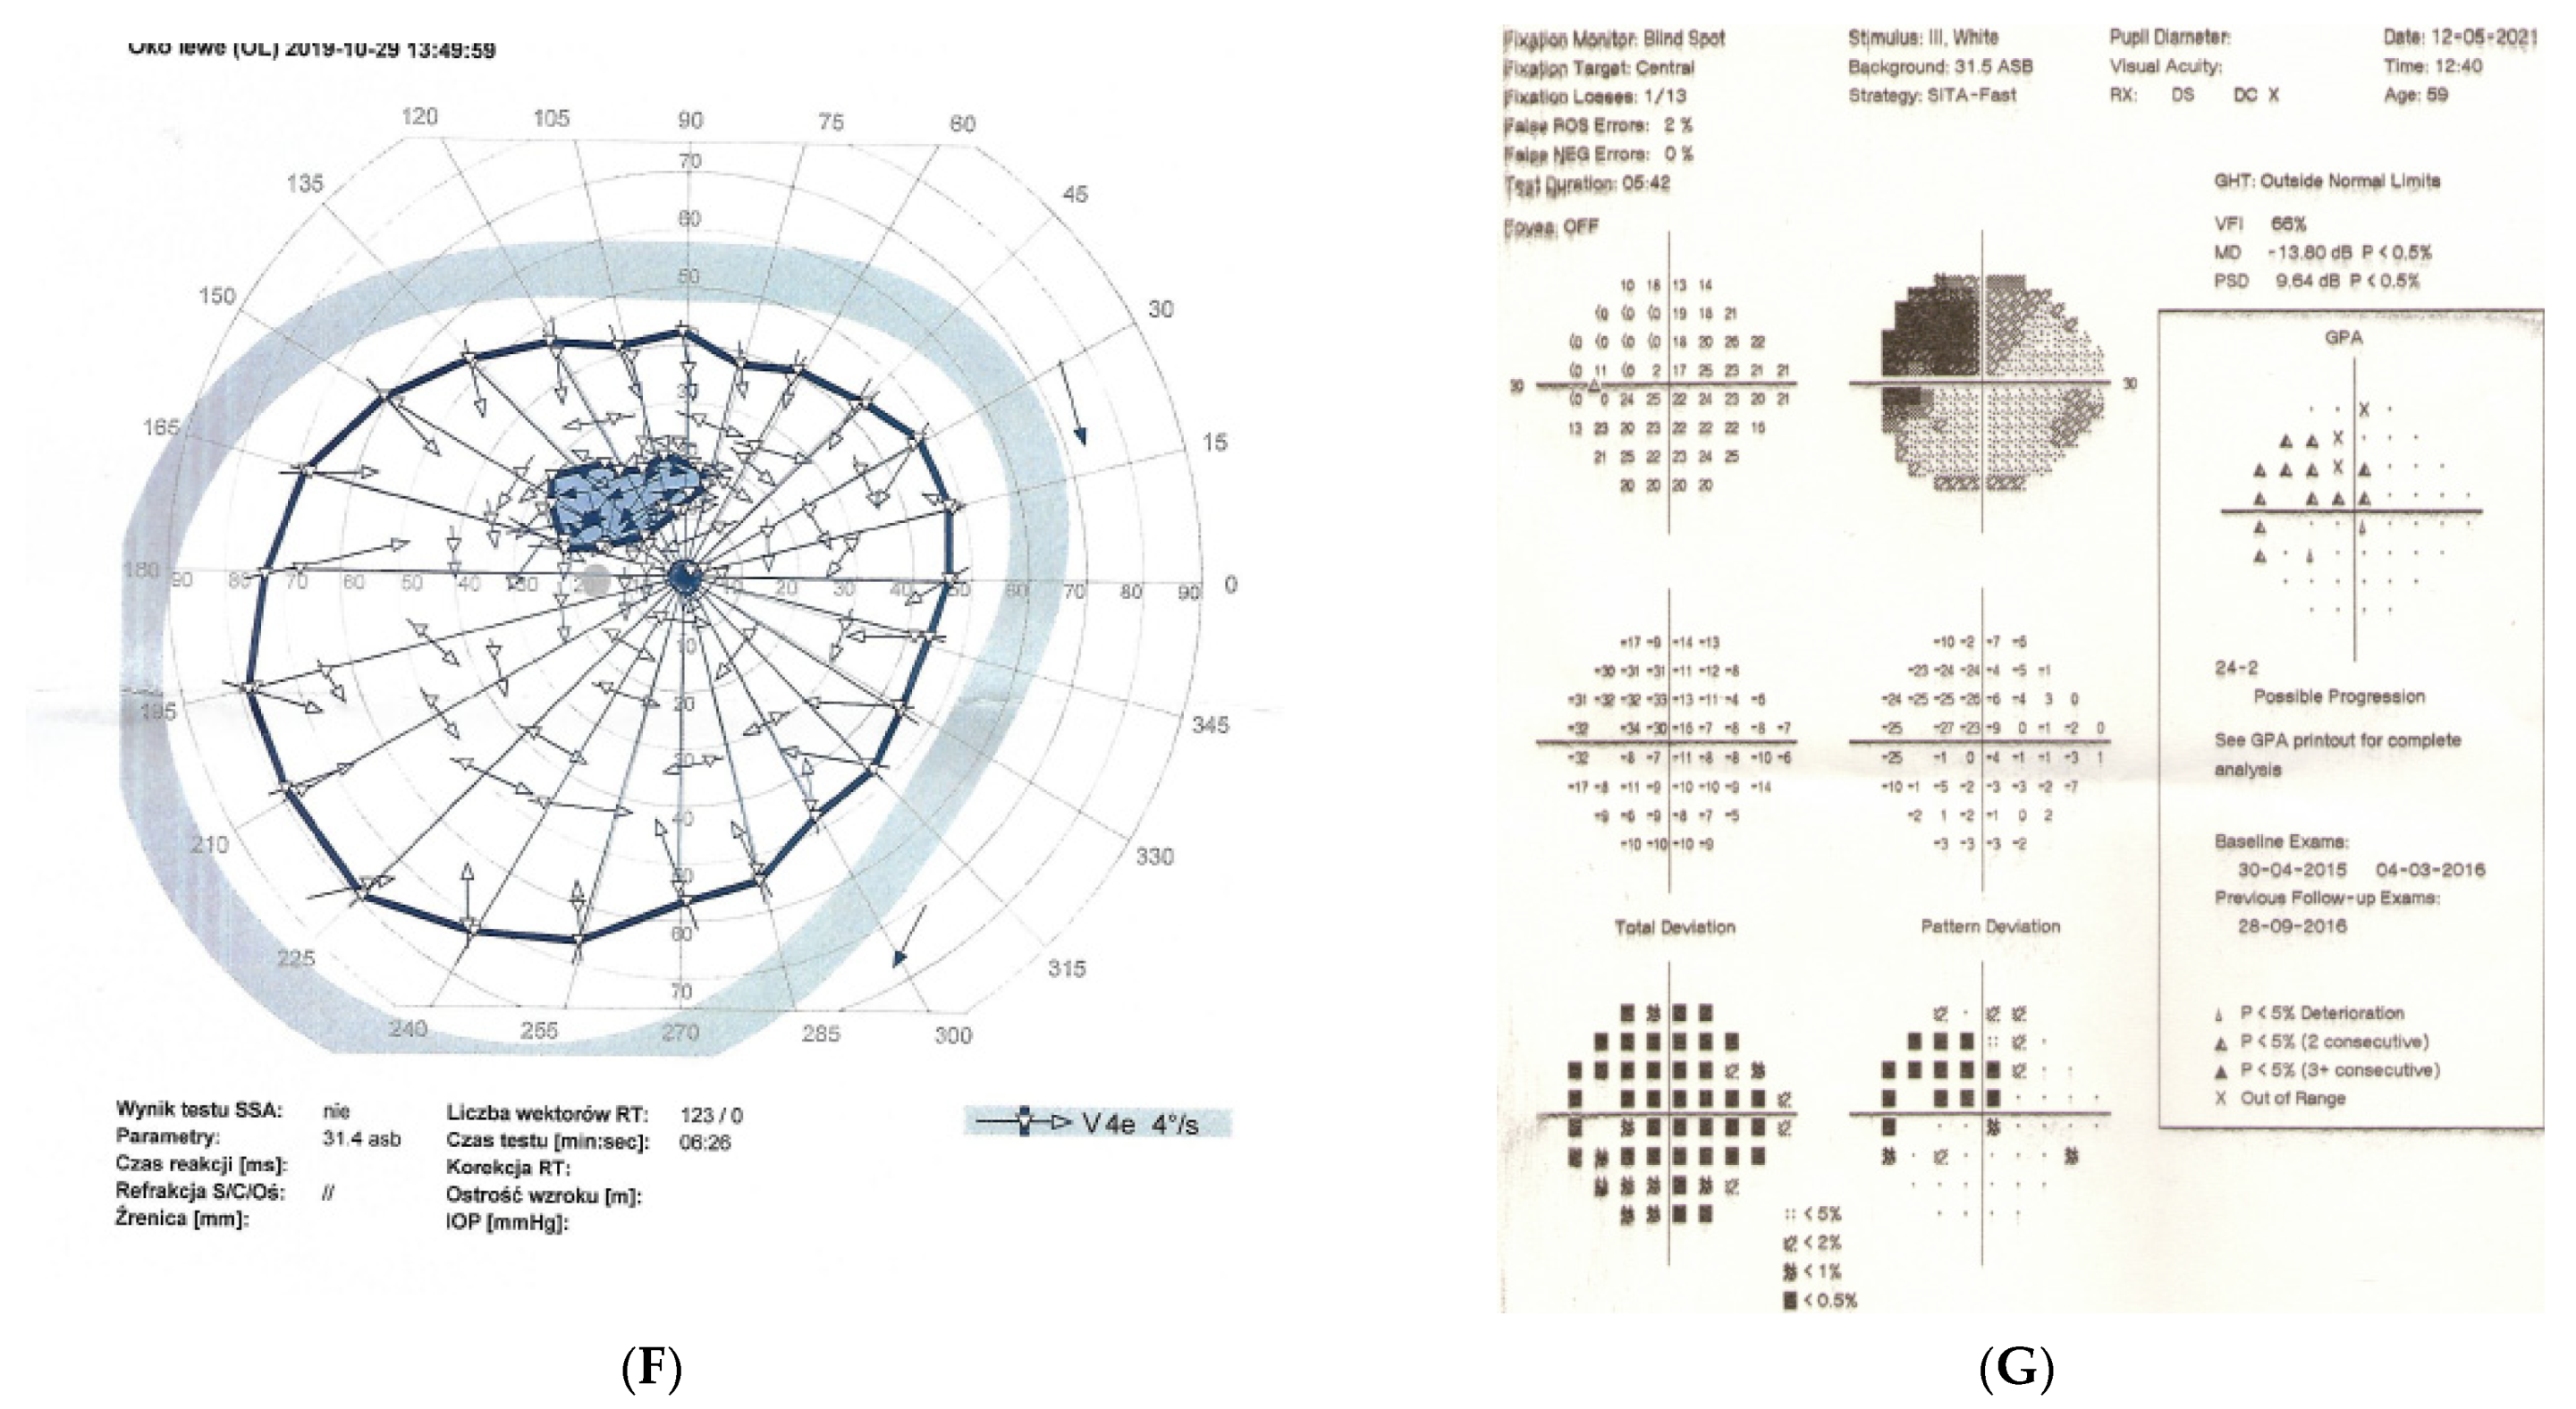

2.4. Case 4

2.5. Case 5

3. Discussion